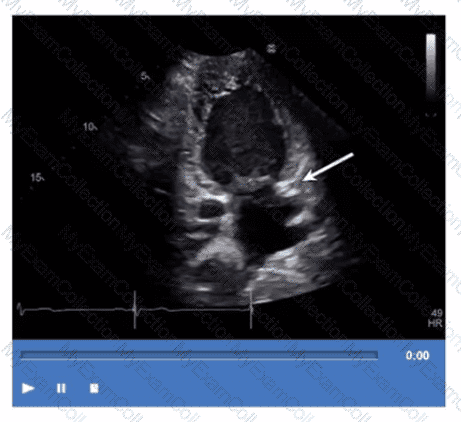

Which step is next in further evaluation of the abnormality shown in this video?